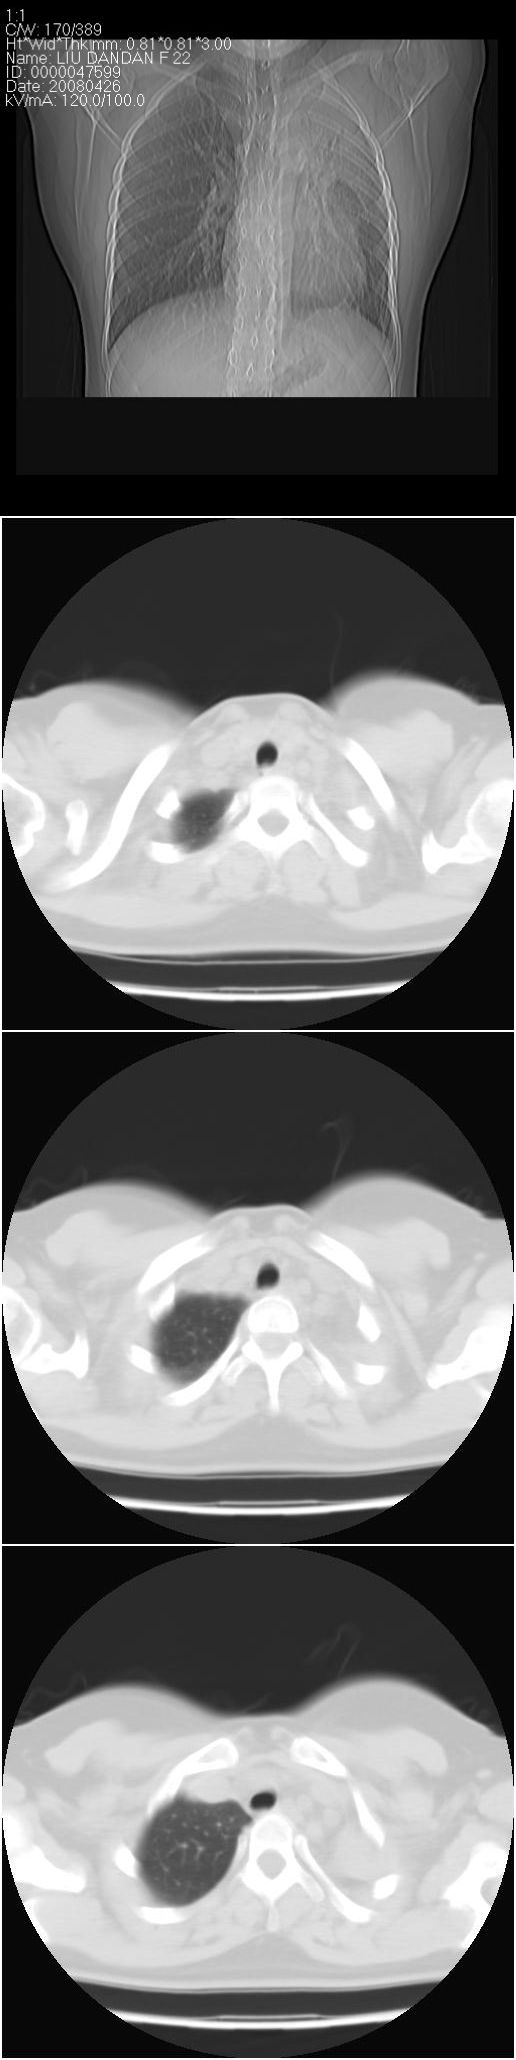

以下是引用光影相伴在2008-4-26 11:32:00的发言:[br]左肺继发性结核伴左肺上叶肺不张。建议:行纤维支气管镜检查排除支气管内膜结核。

以下是引用光影相伴在2008-4-26 11:32:00的发言:[br]左肺继发性结核伴左肺上叶肺不张。建议:行纤维支气管镜检查排除支气管内膜结核。

以下是引用zsl6918在2008-4-26 16:18:00的发言:[br]符合支气管内膜结核的诊断。

以下是引用光影相伴在2008-4-26 11:32:00的发言:[br]左肺继发性结核伴左肺上叶肺不张。建议:行纤维支气管镜检查排除支气管内膜结核。

以下是引用有风的日子在2008-4-26 13:54:00的发言:[br][quote]以下是引用光影相伴在2008-4-26 11:32:00的发言:[br]左肺继发性结核伴左肺上叶肺不张。建议:行纤维支气管镜检查排除支气管内膜结核。